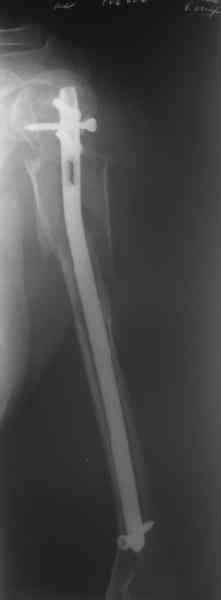

Здесь нет необходимости в серкляже. Вмешиваться на промежуточных отломках приходится, если есть угроза перфорации кожи, или промежуточный отломок попал в фасцию, как пуговица в петлю. В приложении сегментарный оскольчатый перелом плеча в проксимальном отделе, фиксированный больщеберцовым стержнем. Как видите, обошлось без серкляжа. Функция полная.

Это укороченный большеберцовый стержень, которые делает предприятие "ЦИТО".